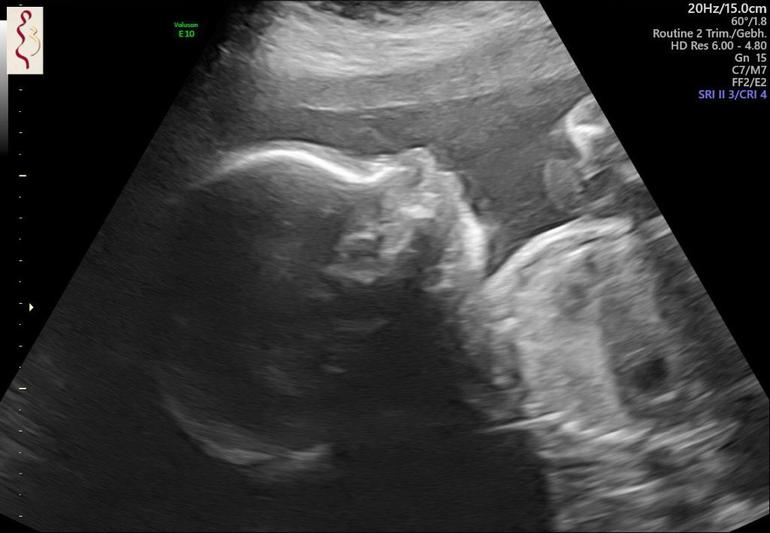

Вчера ходила на дейт с сыночком 🤗 первое что всегда видно на узи это его мужское достоинство... сынок даже и не думает его скрывать 😅🤭 ну а чего так стесняться? мужик же 💪🏼Было у нас опережение головы, мой Г просто смеялся и говорил на мужа своего посмотри🙈 я уже смирилась с тем что у нас будет головастый пацан... а на этом узи голова выровнялась и всего на пару дней опережает 🙈 все очень даже пропорционально, общее опережение сошло на нет, 2 дня чтоли осталось ...

24+2 мы 660 гр и 29,7 см.

Такое УЗИ подробное! Удивительно. Моя гиня внимательно смотрела только жизненноважные органы. Пальчики не считала. Пол посмотрела только по просьбе. Говорит, что такое её интересует в последнюю очередь.

Катя

У моего Г крутой какой-то аппарат и он все смотрит и показывает и 3д на пару сек частенько включает😍 у меня даже видео от узи есть, его аппарат на телефон присылает🤗